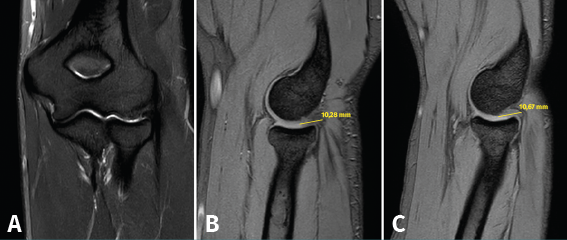

Figura 12. Imágenes de resonancia magnética de un codo izquierdo. Se aprecia una plica posterolateral de codo en el plano coronal (A) y en el plano sagital (B y C).

La RM permite visualizar un tejido similar a un menisco en la cara lateral de la articulación radiocapitelar que se interpone entre la cabeza radial y el capitellum (Figura 12). Las plicas pueden localizarse en el lado anterolateral, en el posterolateral o en ambos, siendo más frecuente la localización posterolateral. La RM nos permite medir su grosor, así como su longitud. El grosor medio de las plicas patológicas suele estar en torno a 3,7 ± 1,0 mm, que es significativamente más grueso que el valor de una plica normal (1,8 ± 1,4 mm)(6). La longitud del pliegue medida en coronal y sagital (9,4 ± 1,6 y 8,2 ± 1,7 mm, respectivamente) también es mayor que los valores normales (3,9 ± 1,5 y 4,3 ± 1,5 mm)(35). Se debe tener en cuenta que no todas las plicas son patológicas ni sintomáticas, independientemente de su tamaño. Es necesario apreciar edema en el tejido que conforma la plica o a su alrededor y tener una clínica compatible. La artrorresonancia puede ser de utilidad en caso de dudas.